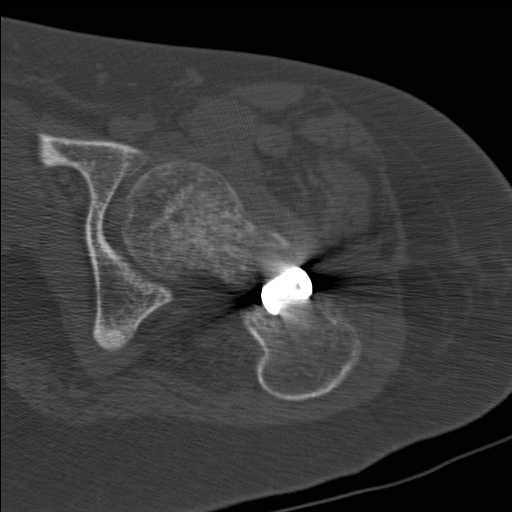

Добрый день уважаемые коллеги. Во такая ситуация. Девушка 19 лет травму получила в мае 2016г (изолированная травма, трансцервикальный перелом шейки левого бедра). Соматически здорова. Лечилась по месту жительства скелетным вытяжением в течении 1 месяца.

Затем переведена в наше учреждение. 18 июня выполнена операция, детали где , кто и как уточнять не имеет смысла( из протокола операции: выполнялась передняя артротомия, репозиция под визуальным контролем) . Учитывая характер выполненного остеосинтеза, после операции постельный режим 6 недель. Снимки в хронологии все выкладываю. КТ контроль сделан 2.09.16. для оценки состояния головки бедра. Помогите, определиться с дальнейшей тактикой.

согласен с Александром Николаевичем, надо пытаться сохранить сустав (в т.ч. его страдающее кровоснабжение. Судя по КТ Сохраняется ретроверсия шейки бедра. Вероятны трудности с репозицией последней. Для создания правильного направления шеечных винтов (Винта) возможно придется делать вальгусно-антекурвационную межвертельную остетомию, тем самым произвести разгибание в т/бедренном суставе проксимального отломка. И ретроверсия станет в большей степени вальгусом. То есть точка входа для гвоздя должна быть кзади от торчащей части прорезавшегося клинка со всеми вытекающими перемещениями проксимальной части.